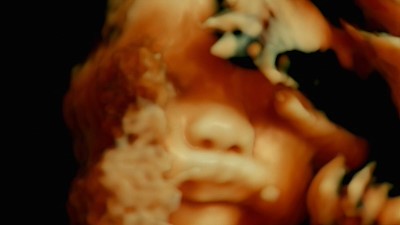

Vor fünf Jahrhunderten öffnete der Anatom Andreas Vesalius zum ersten Mal den menschlichen Körper für den Blick der Wissenschaft. Dieser Film öffnet ihn heute für das Kino. Wir entdecken, dass das menschliche Fleisch eine unerhörte Landschaft ist, die nur dank der Blicke und der Aufmerksamkeit der anderen existiert. Krankenhäuser und Pflegeeinrichtungen sind Laboratorien, die alle Körper der Welt miteinander verbinden. Der Film geht buchstäblich unter die Haut.